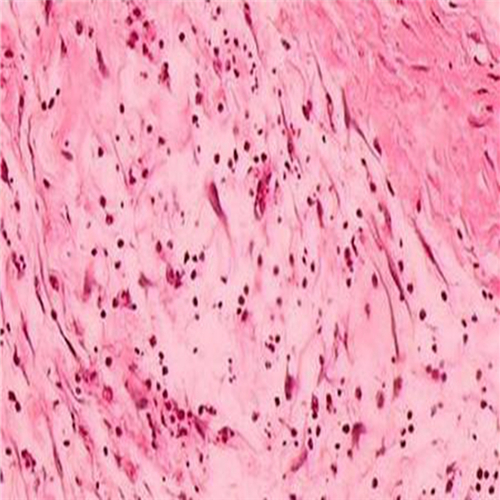

直腸息肉細胞

直腸息肉惡變細胞

直腸息肉的細胞圖